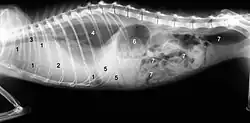

Die klassische „feuchte Form“ äußert sich in Flüssigkeitsansammlungen in der Bauchhöhle (Bauchwassersucht, Aszites) oder in der Brusthöhle (Pleuraerguss). Die Flüssigkeitsansammlungen in der Bauchhöhle können als Umfangsvermehrung mit Fluktuation meist klinisch diagnostiziert werden. Flüssigkeitsansammlungen in der Brusthöhle können zu schwerer Atemnot führen. Eine Punktion liefert eine gelbliche, fadenziehende, viskose Flüssigkeit. Die Tatsache, dass es sich hierbei um ein proteinreiches Exsudat handelt, welches in seiner Erscheinungsform recht typisch ist, ist ein wesentliches diagnostisches Kriterium.

Flüssigkeitsansammlungen in den Körperhöhlen („feuchte Form“) sowie ein vermehrter Gehalt an Globulinen im Blut (Hyperglobulinämie) sind bereits deutliche Indizien. Bestimmte Veränderungen des Blutbildes (mittlere bis schwere Anämie, Neutrophilie und Leukopenie) sind weitere Verdachtsmomente.